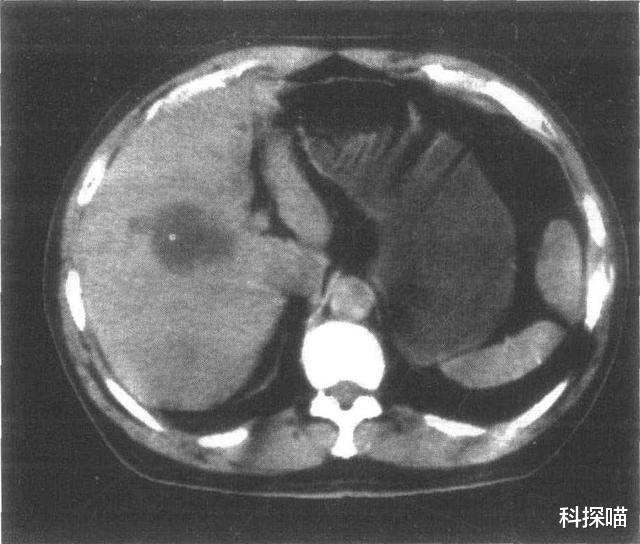

肝囊肿

肝囊肿是临床上非常常见的一种疾病 , 很多人在查体的过程中 , 经过B超、CT或者核磁都会发现 , 肝上可能会有大大小小的肝囊肿 , 数目从1个到多个不等 , 尤其老年人更容易好发 。

一般肝囊肿对人身体健康 , 危害不大 , 不会变成癌 , 不会转变成肿瘤这一类的疾病 。 肝囊肿自发性破裂的概率非常之罕见 。

但是有些肝囊肿 , 随着不断的长大 , 或者长在特殊的部位 , 可能会产生一些压迫症状 , 或者会对邻近的器官产生影响 。 如果出现了情况 , 一般需要治疗 。